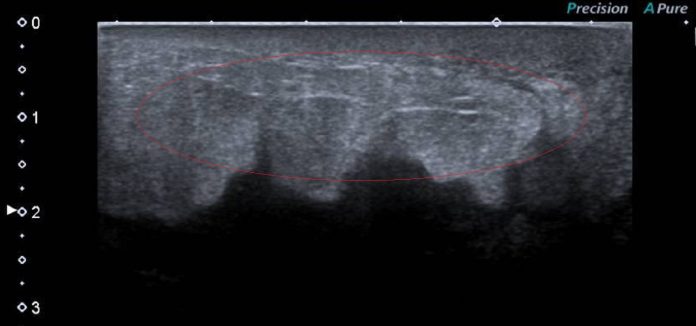

:張姓婦人的胸部超音波,顯示只是組織水腫,沒有明顯的腫瘤。(彰化醫院提供)

李忠懷醫師表示,右乳房的腫脹並未呈現典型的乳癌跡象,最初的超音波顯示僅為組織水腫,沒有明顯的腫瘤。進一步的切片檢查結果令所有人都感到震驚,原來是左肺的癌細胞透過淋巴系統,轉移至右乳。